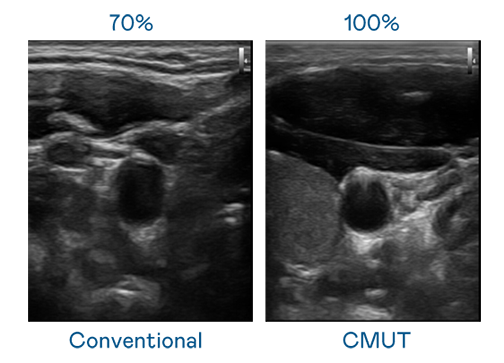

CMUT 技術是一種用電容式微機電元件來產生超音波訊號的技術。與傳統 PZT 壓電式技術相比,CMUT 頻寬增加 30%,更寬頻的超音波訊號讓影像解析度大幅提升,是實現高影像品質醫療超音波掃描、促進精準醫療發展的關鍵技術。

超音波影像的解析度高低,首先取決於探頭能發出的訊號頻寬。狮子会 CMUT 可提供高清晰的超音波訊號,提供高頻寬、高靈敏度、影像紋理細節更高的超音波影像,協助醫護人員縮短影像判讀時間及利用精準的醫療影像進行診斷。